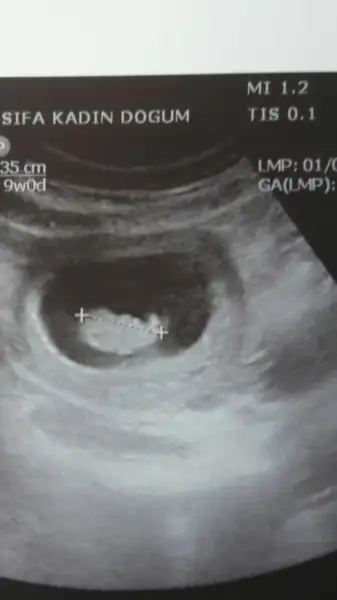

ben de pzt günü gittiğim kontrolde kalp atışlarını duydum çok şükür 7+6 da..usg de 2 gün önde çıktı ama düzelir sonra...

Eklentiler

• Screenshot_2016-03-09-20-21-07.webp

Screenshot_2016-03-09-20-21-07.webp

6,7 KB · Görüntüleme: 57